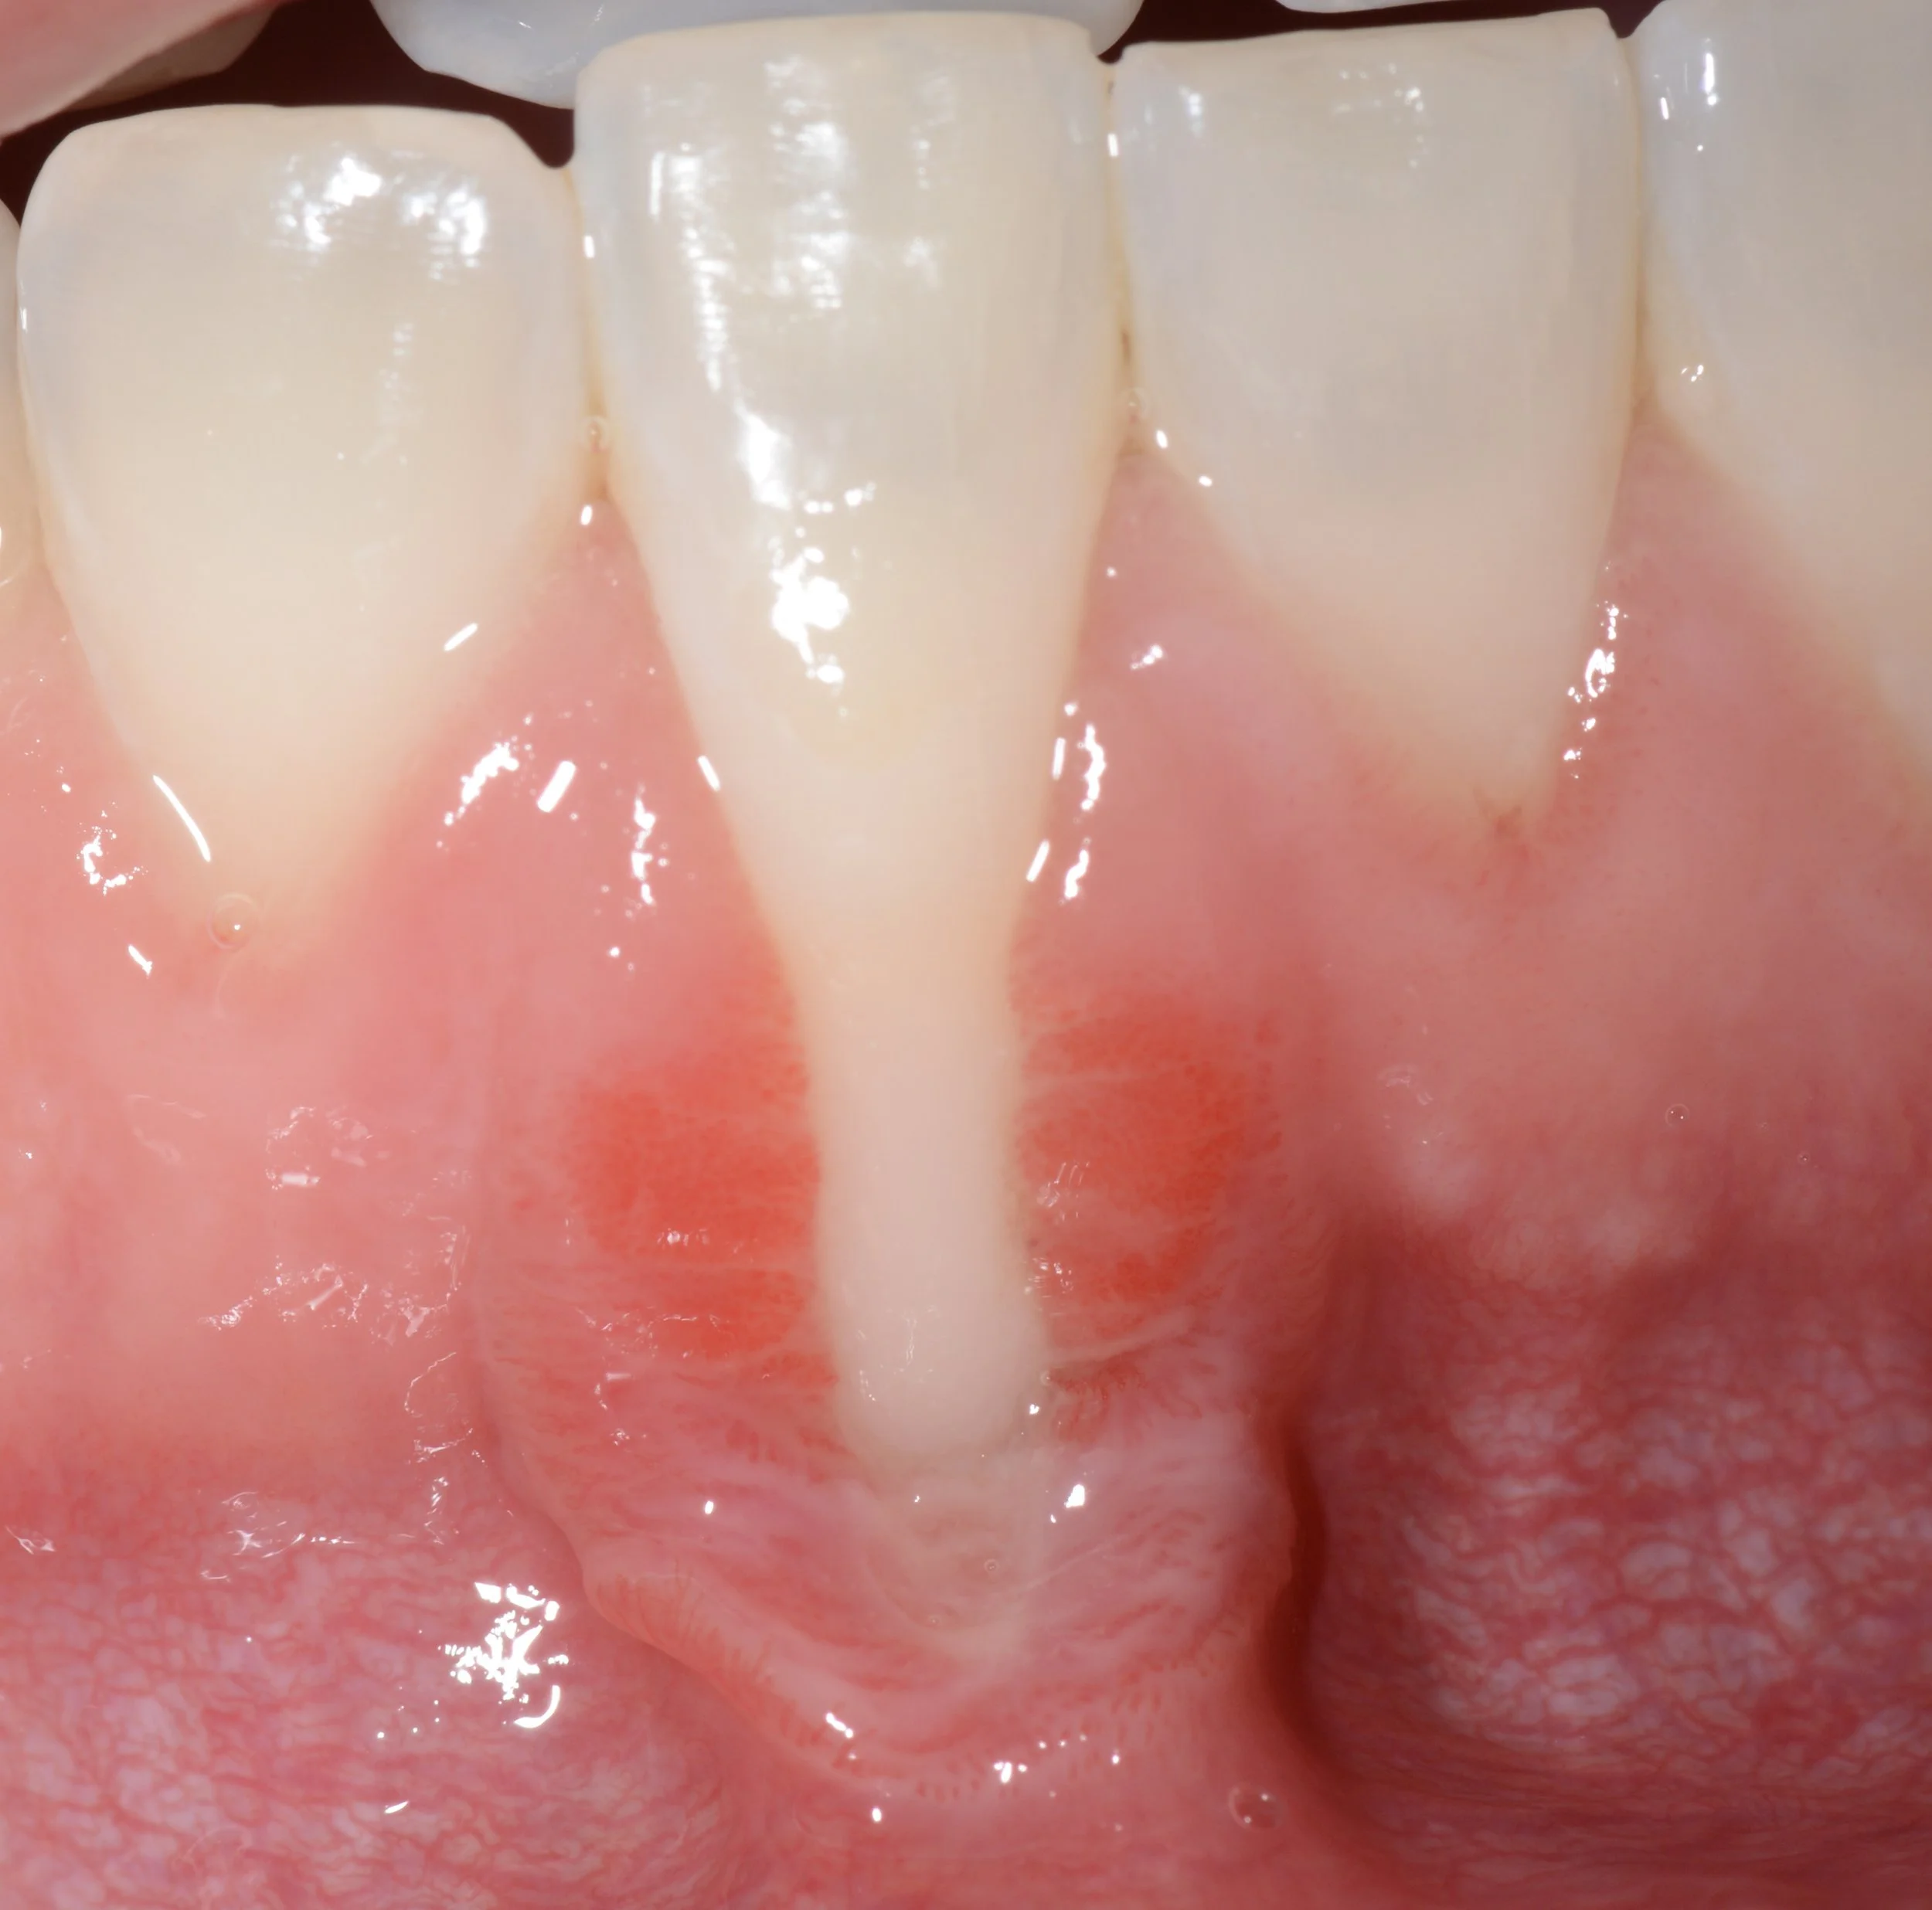

Objectif : Augmenter la quantité de gencive attachée et recouvrir des racines dentaires exposées.

• Sensibilité dentaire

• Inesthétique

• Progression des récessions

• Manque de gencive